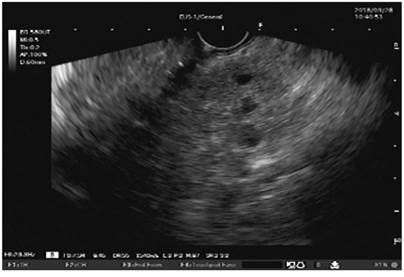

Dilation of the Wirsung duct or stones within this duct (Figure 2)

Figure 2 Dilation of the Wirsung duct and calculi within it, seen with Fujinon’s linear endosonography (image courtesy of the Union of Surgeons SAS, Lázaro Arango).